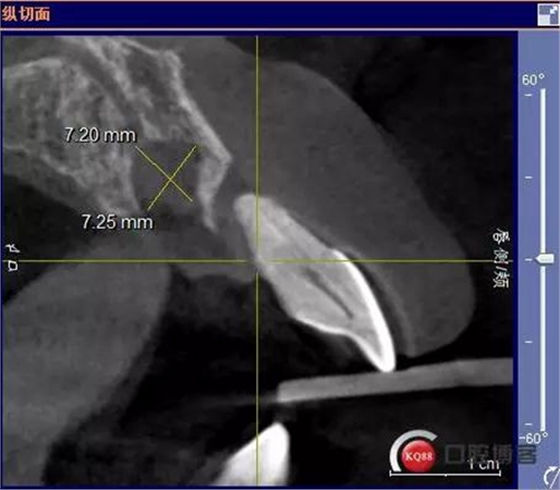

術(shù)前CBCT